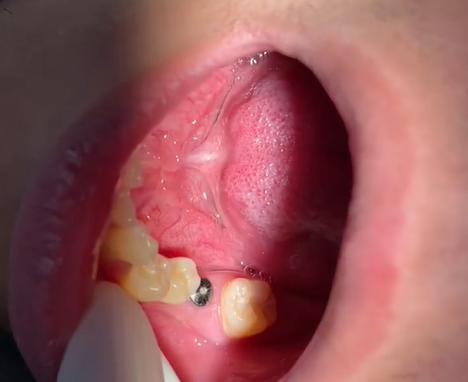

- 植入种植体:在局部麻醉下,通过微创手术将种植体植入牙槽骨内,手术时间约30-60分钟,术后无需缝合或可吸收线缝合,7-10天拆线。

- 骨结合期:这是种植牙成功的关键阶段,种植体表面的特殊结构(如钛的粗糙表面)会引导牙槽骨细胞附着、生长,最终与种植体形成牢固的“骨整合”,此期间需避免种植体受力,一般需等待3-6个月(即刻种植或即刻负重技术可缩短至1-3个月,需符合严格适应证)。